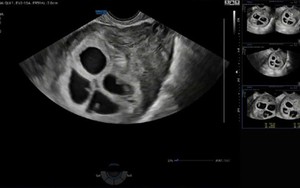

Cực hiếm gặp: Bệnh viện Phụ Sản Hà Nội ghi nhận 1 sản phụ mang thai 4 tự nhiên, tỷ lệ chỉ khoảng 1/700.000 - 800.000 ca

Sống khỏe 2025-07-05T17:02:00Trường hợp đặc biệt với tỷ lệ hiếm chỉ 1/700.000 ca mang thai tự nhiên khiến giới chuyên môn lẫn cộng đồng không khỏi bất ngờ.